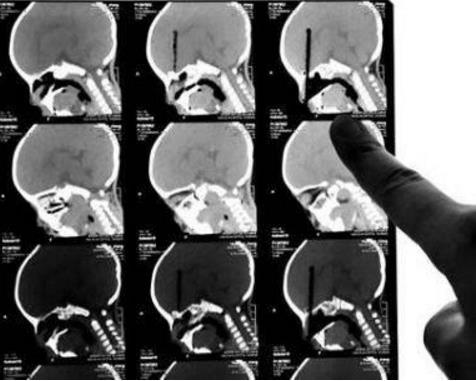

建议2——3岁左右的孩子使用筷子或者笔时,父母必须在旁边看护。已有孩子不慎跌倒,导致筷子或笔扎入头部的悲剧发生了。

一女童玩耍时,筷子插入颅腔